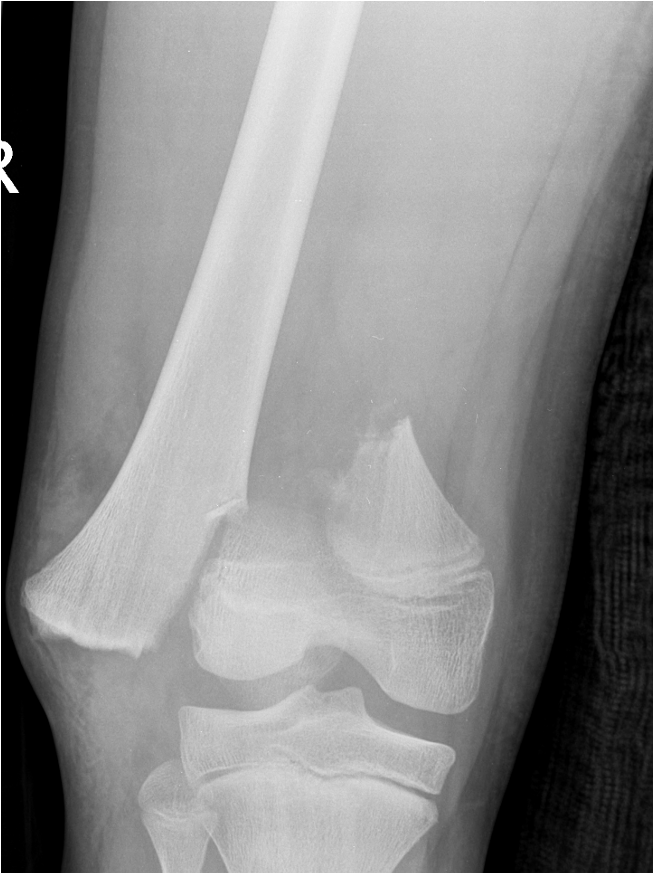

Growth plate fractures - Salter Harris Type II most common 60%

Distal Femoral Fracture SH2 APDistal Femoral Fracture SH2 Lateral

Salter Harris Type I

SH2SH2

Salter Harris Type II